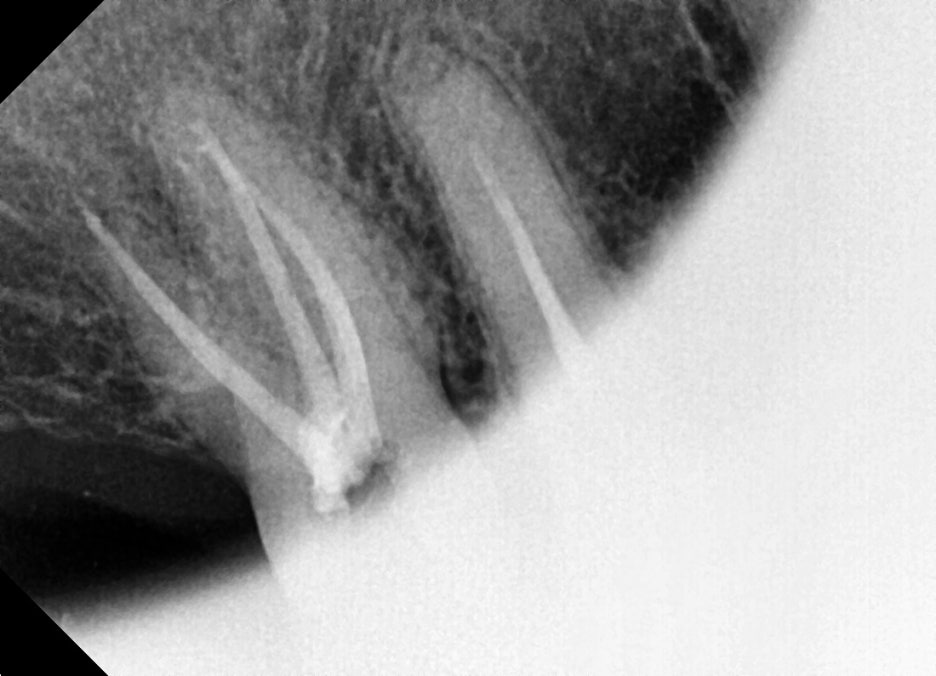

정밀 파악을 위해 추가로 치근단 엑스레이를 촬영했고, 실제로 치아 뿌리 끝까지 염증이 퍼져 있는 것이 확인되었습니다. 이 단계에서 신경치료 계획을 확정했습니다.

1주 후 내원한 2차 치료에서는 근관 내부에 남아 있는 미세 염증 조직을 제거하는 과정이 진행되었습니다.

근관의 형태가 안정적으로 정리되면 그다음 단계로 최종 충전(근관충전)을 준비할 수 있습니다.